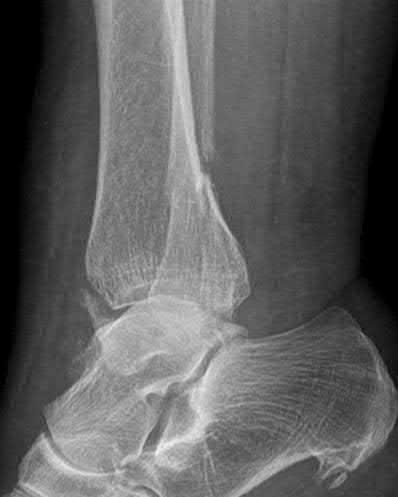

A 28-year-old male sustains a severe hyper-dorsiflexion injury to his ankle in a motor vehicle accident, resulting in a Hawkins Type III talar neck fracture. Which of the following arteries provides the predominant blood supply to the body of the talus, placing it at significant risk for avascular necrosis in this injury?

Correct Answer: Artery of the tarsal canal

Explanation:

The artery of the tarsal canal, which is a branch of the posterior tibial artery, provides the dominant blood supply to the talar body. In a Hawkins Type III fracture (talar neck fracture with subtalar and tibiotalar dislocation), the blood supply from the artery of the tarsal canal, the artery of the sinus tarsi, and capsular vessels are disrupted, leading to an avascular necrosis (AVN) rate approaching 100%.